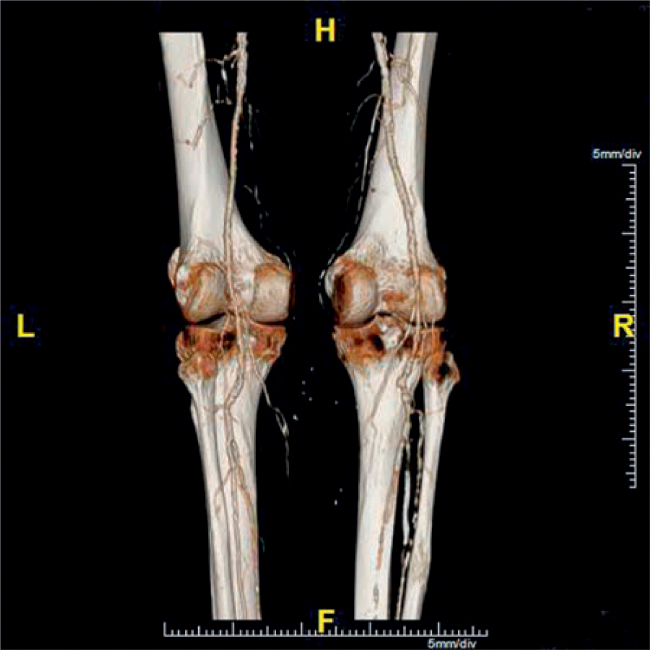

Bệnh động mạch ngoại biên (PAD) là một bệnh của quá trình lão hóa với tỷ lệ hiện mắc là 10% ở người trên 65 tuổi và 30% ở người ở độ tuổi 80, biểu hiện bằng chứng đau cách hồi hoặc các triệu chứng thiếu máu chi nguy kịch. Các triệu chứng thường xuất hiện ở phần xa so với mức độ hẹp. Nếu bệnh nhân hoạt động, đau cách hồi là triệu chứng điển hình; nếu bệnh nhân không hoạt động, PAD có thể biểu hiện bằng đau khi nghỉ, loét, đỏ da khi hạ thấp chi, hoặc hoại tử (Hình 25.1). Khi chứng đau cách hồi tăng đột ngột, phải xem xét đến huyết khối tại chỗ hoặc một biến cố thuyên tắc. Biểu hiện lâm sàng của xơ vữa động mạch tắc nghẽn (tắc động mạch cấp tính) được mô tả bằng sáu chữ P: pain (đau), pallor (xanh xao), paresthesia (dị cảm), paralysis (liệt), pulselessness (mất mạch), và polar (cảm giác lạnh). Chi có nguy cơ bị cắt cụt nếu lưu lượng máu không được phục hồi kịp thời (Hộp 25.2).